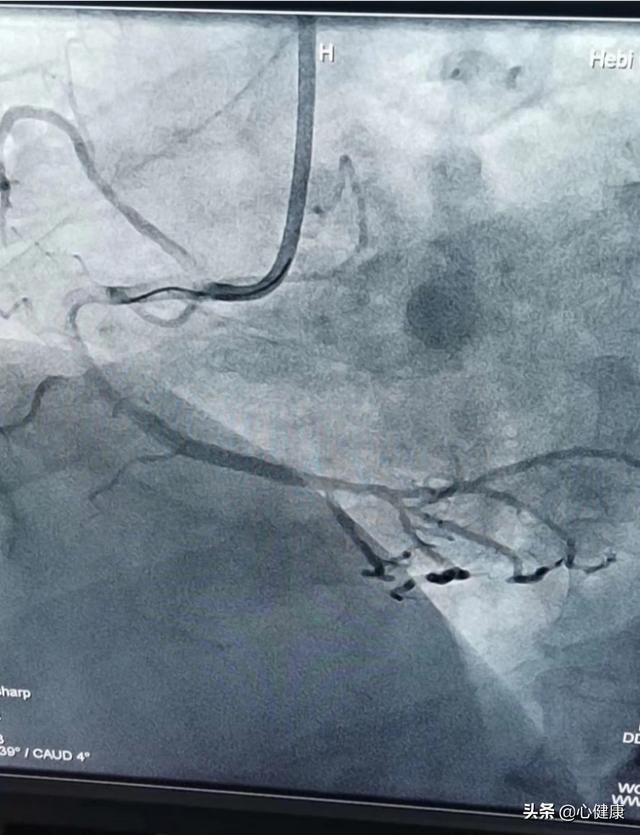

Premièrement, une sténose des artères coronaires supérieure à 70 % indique que la sténose s'est aggravée. En général, une sténose de plus de 50 % des artères coronaires peut entraîner une insuffisance de l'apport sanguin aux artères coronaires et une maladie coronarienne peut déjà être diagnostiquée. Une sténose de plus de 70 % des artères coronaires est définitivement considérée comme une sténose plus grave, qui peut entraîner des épisodes d'angine de poitrine à l'effort. Mais même avec une sténose de 70 %, tant qu'il n'y a pas d'augmentation drastique de la consommation d'oxygène due à des activités intenses, l'approvisionnement en sang pour les activités quotidiennes générales peut toujours être assuré et il n'y a pas lieu de s'inquiéter outre mesure. Cependant, tous les patients souffrant d'une maladie coronarienne doivent prendre du métoprolol pour contrôler la fréquence ventriculaire, réduire la consommation d'oxygène du myocarde et diminuer l'apparition de l'angine de poitrine.

Quant à savoir si la pose d'un stent est nécessaire lorsque la sténose de l'artère coronaire dépasse 70 %, il convient de procéder à une évaluation complète en fonction de l'état et du site de la sténose, et aucune généralisation n'est possible. Pour les patients souffrant d'un infarctus aigu, plus le stent est placé tôt, mieux c'est ; pour les patients souffrant d'un syndrome coronarien aigu sans sus-décalage du segment ST (angor instable ou infarctus du myocarde sans sus-décalage du segment ST), et pour ceux du groupe à risque intermédiaire ou supérieur qui présentent des facteurs de risque cardiovasculaire plus importants, le moment de l'implantation d'un stent doit être choisi différemment. Chez les patients souffrant d'angor stable, il n'y a pas de différence statistique en termes de pronostic et d'amélioration symptomatique entre la pose ou non d'un stent, même si la sténose coronaire atteint 70 %. Le pontage aorto-coronarien peut être plus approprié en cas de maladie coronarienne à trois branches, de maladie du tronc principal gauche ou de maladie de bifurcation du tronc principal gauche, de maladie à la bifurcation d'une grosse artère coronaire, de maladie coronarienne associée à un anévrisme de la paroi ventriculaire, de perforation du septum interventriculaire, d'insuffisance de la valve mitrale ou d'autres anomalies structurelles endocardiques.

Enfin, que l'on opte ou non pour la pose d'une endoprothèse coronaire, celle-ci ne remplace pas un traitement médical standardisé tel que les hypolipidémiants de type statine pour la stabilisation de la plaque et les antiplaquettaires tels que l'aspirine pour l'inhibition de l'agrégation plaquettaire.